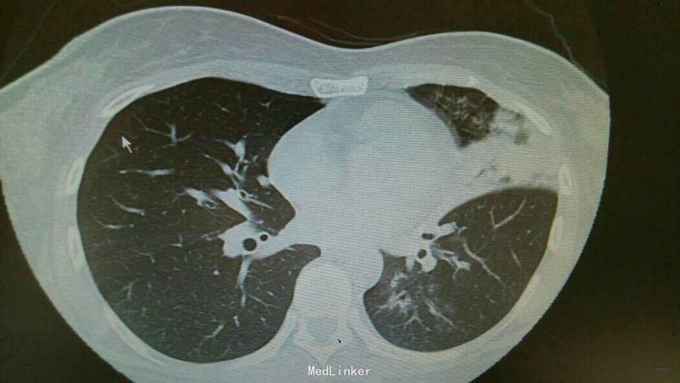

主诉:发热伴咳嗽咳痰6天。 病史:患者6天前无明显诱因出现发热,最高体温39.3度,伴有咳嗽,咳痰,咳黄色粘液痰,无畏寒寒战,无头晕头痛,为求治疗,入住我科。

查体:双肺呼吸音粗,双下肺可闻及湿罗音。心腹无异常。 辅查:双肺炎症,左侧可见多发斑片状,渗出实变影,边缘模糊,部分邻近胸膜,粘连。

诊断:肺炎支原体费炎。 治疗:入院予以抗感染,止咳化痰等治疗。治疗后复查胸片,左中下肺炎症好转。